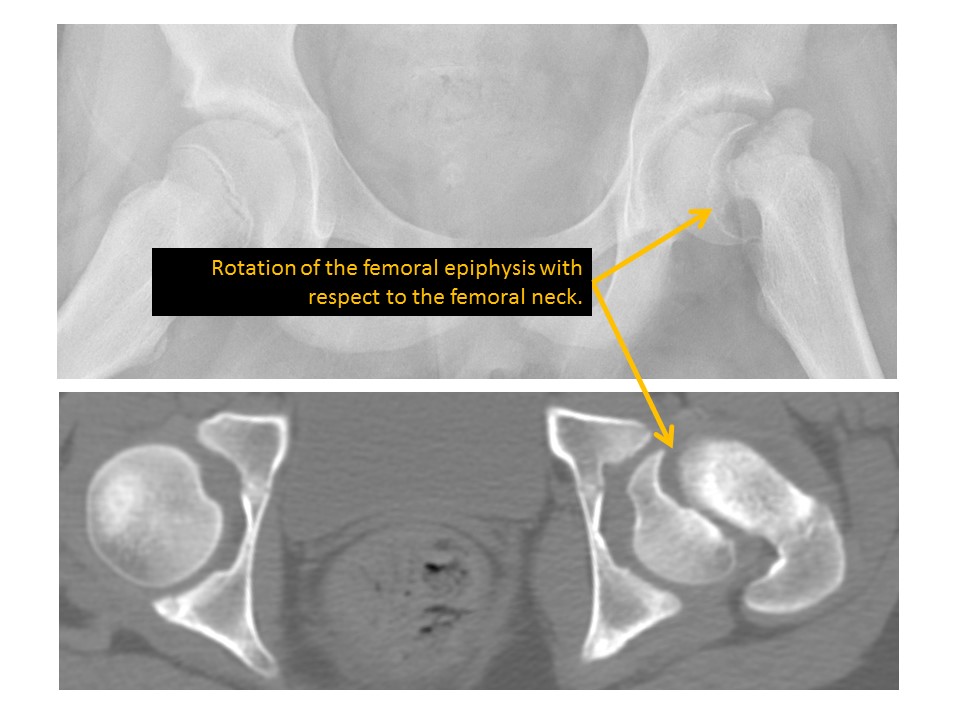

HIPS/PROXIMAL FEMURS

1. 1-Hip/pelvis fracture/malalignment as discussed above.